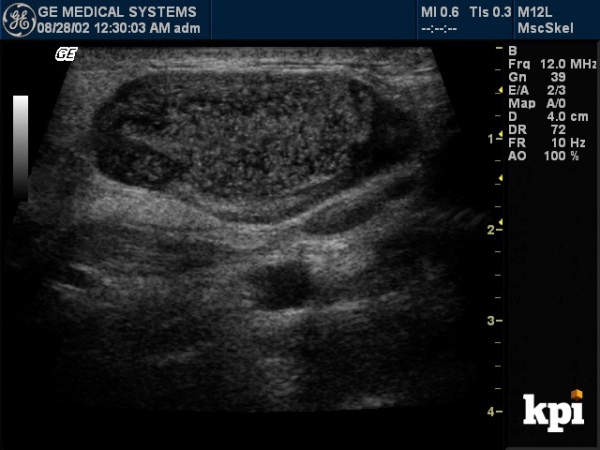

Николай, на вашем сканере должна быть функция Виртуального конвекса на линейном датчике.

Найдите ее и тогда ваша линейкса превратится в конвекс и щитовидка начнет в основном влезать во весь экран.

Получится примерно так:

Николай, на медисоне EKO 7 есть кнопка "Трапеция" -это кнопка под экраном панели управления, она действует в режиме линейного датчика и разворачивает углы как показал Дмитрий